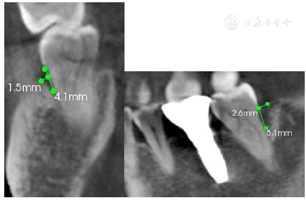

47叩痛(-),不松动,远中及颊侧中央PD7~9 mm,余位点PD3~4 mm,BI2-3,颊侧中央牙龈退缩约2 mm,无附着龈,舌侧牙龈无明显异常(图6,图7)。正中合未及早接触,侧方合未及合干扰,cbct示47颊侧及远中牙槽骨吸收超过根长2/3,颊侧骨缺损深约9 mm,宽约4 mm,远中骨缺损深约10 mm,宽约7 mm(图8,图9)

术后6年,47牙龈无明显红肿,远中及颊侧中央PD 3~4 mm,颊侧退缩根面得到覆盖,颊侧中央出现附着龈,宽约2 mm,BI1,X线片示远中骨缺损明显修复(图25,图26,图27),CBCT示47颊侧骨缺损深约4 mm,宽约1.5 mm,远中骨缺损深约5 mm,宽约3 mm,较初诊时颊侧及远中骨缺损均得到明显修复且骨高度保持稳定(图28,图29)。